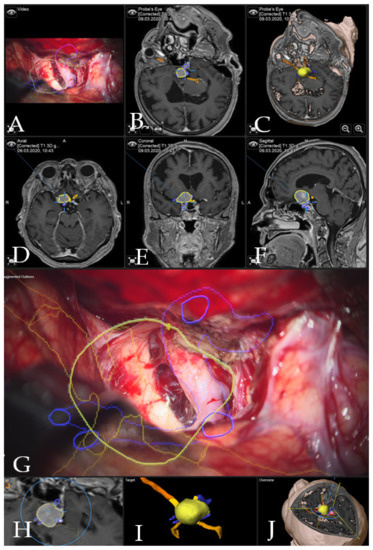

Figure 3. Navigation and AR support during surgery (patient no. 28). (A) Microscope video with head-up display and 3-dimensional (3D) visualization of the segmented objects (tumor in yellow, carotid and anterior cerebral arteries in blue, optic chiasm in yellow). (B,C) Probe’s eye view in 2D and 3D mode. Navigation display in (D) axial, (E) coronal and (F) sagittal view with the segmented objects (focus on the tumor following debulking). (G) AR display on video screen with the 3D outline of tumor, carotid arteries, optic nerves and chiasm. (H) Corresponding probe’s eye view. (I) Target view (tumor and further objects outside of the focus plane are visualized) and (J) video plane in relation to the 3D objects.

Case 1: Patient no. 28 was a 77-year-old female patient with right clinoidal meningioma who experienced visual field deficits and visual deterioration. A complete resection of the tumor was performed via right fronto-temporal craniotomy. AR support facilitated the course of the resection with prompt localization of the segmented carotid and cerebral arteries, as well as the optic chiasm, providing surgical precision throughout the procedure. Figure 3 demonstrates navigation and AR support at the beginning of the tumor resection and Figure 4 shows the microscopic view following the gross total resection of the tumor. The patient recovered fully and was neurologically intact. Operative video has been added to Supplementary Materials: Video Pt 28.